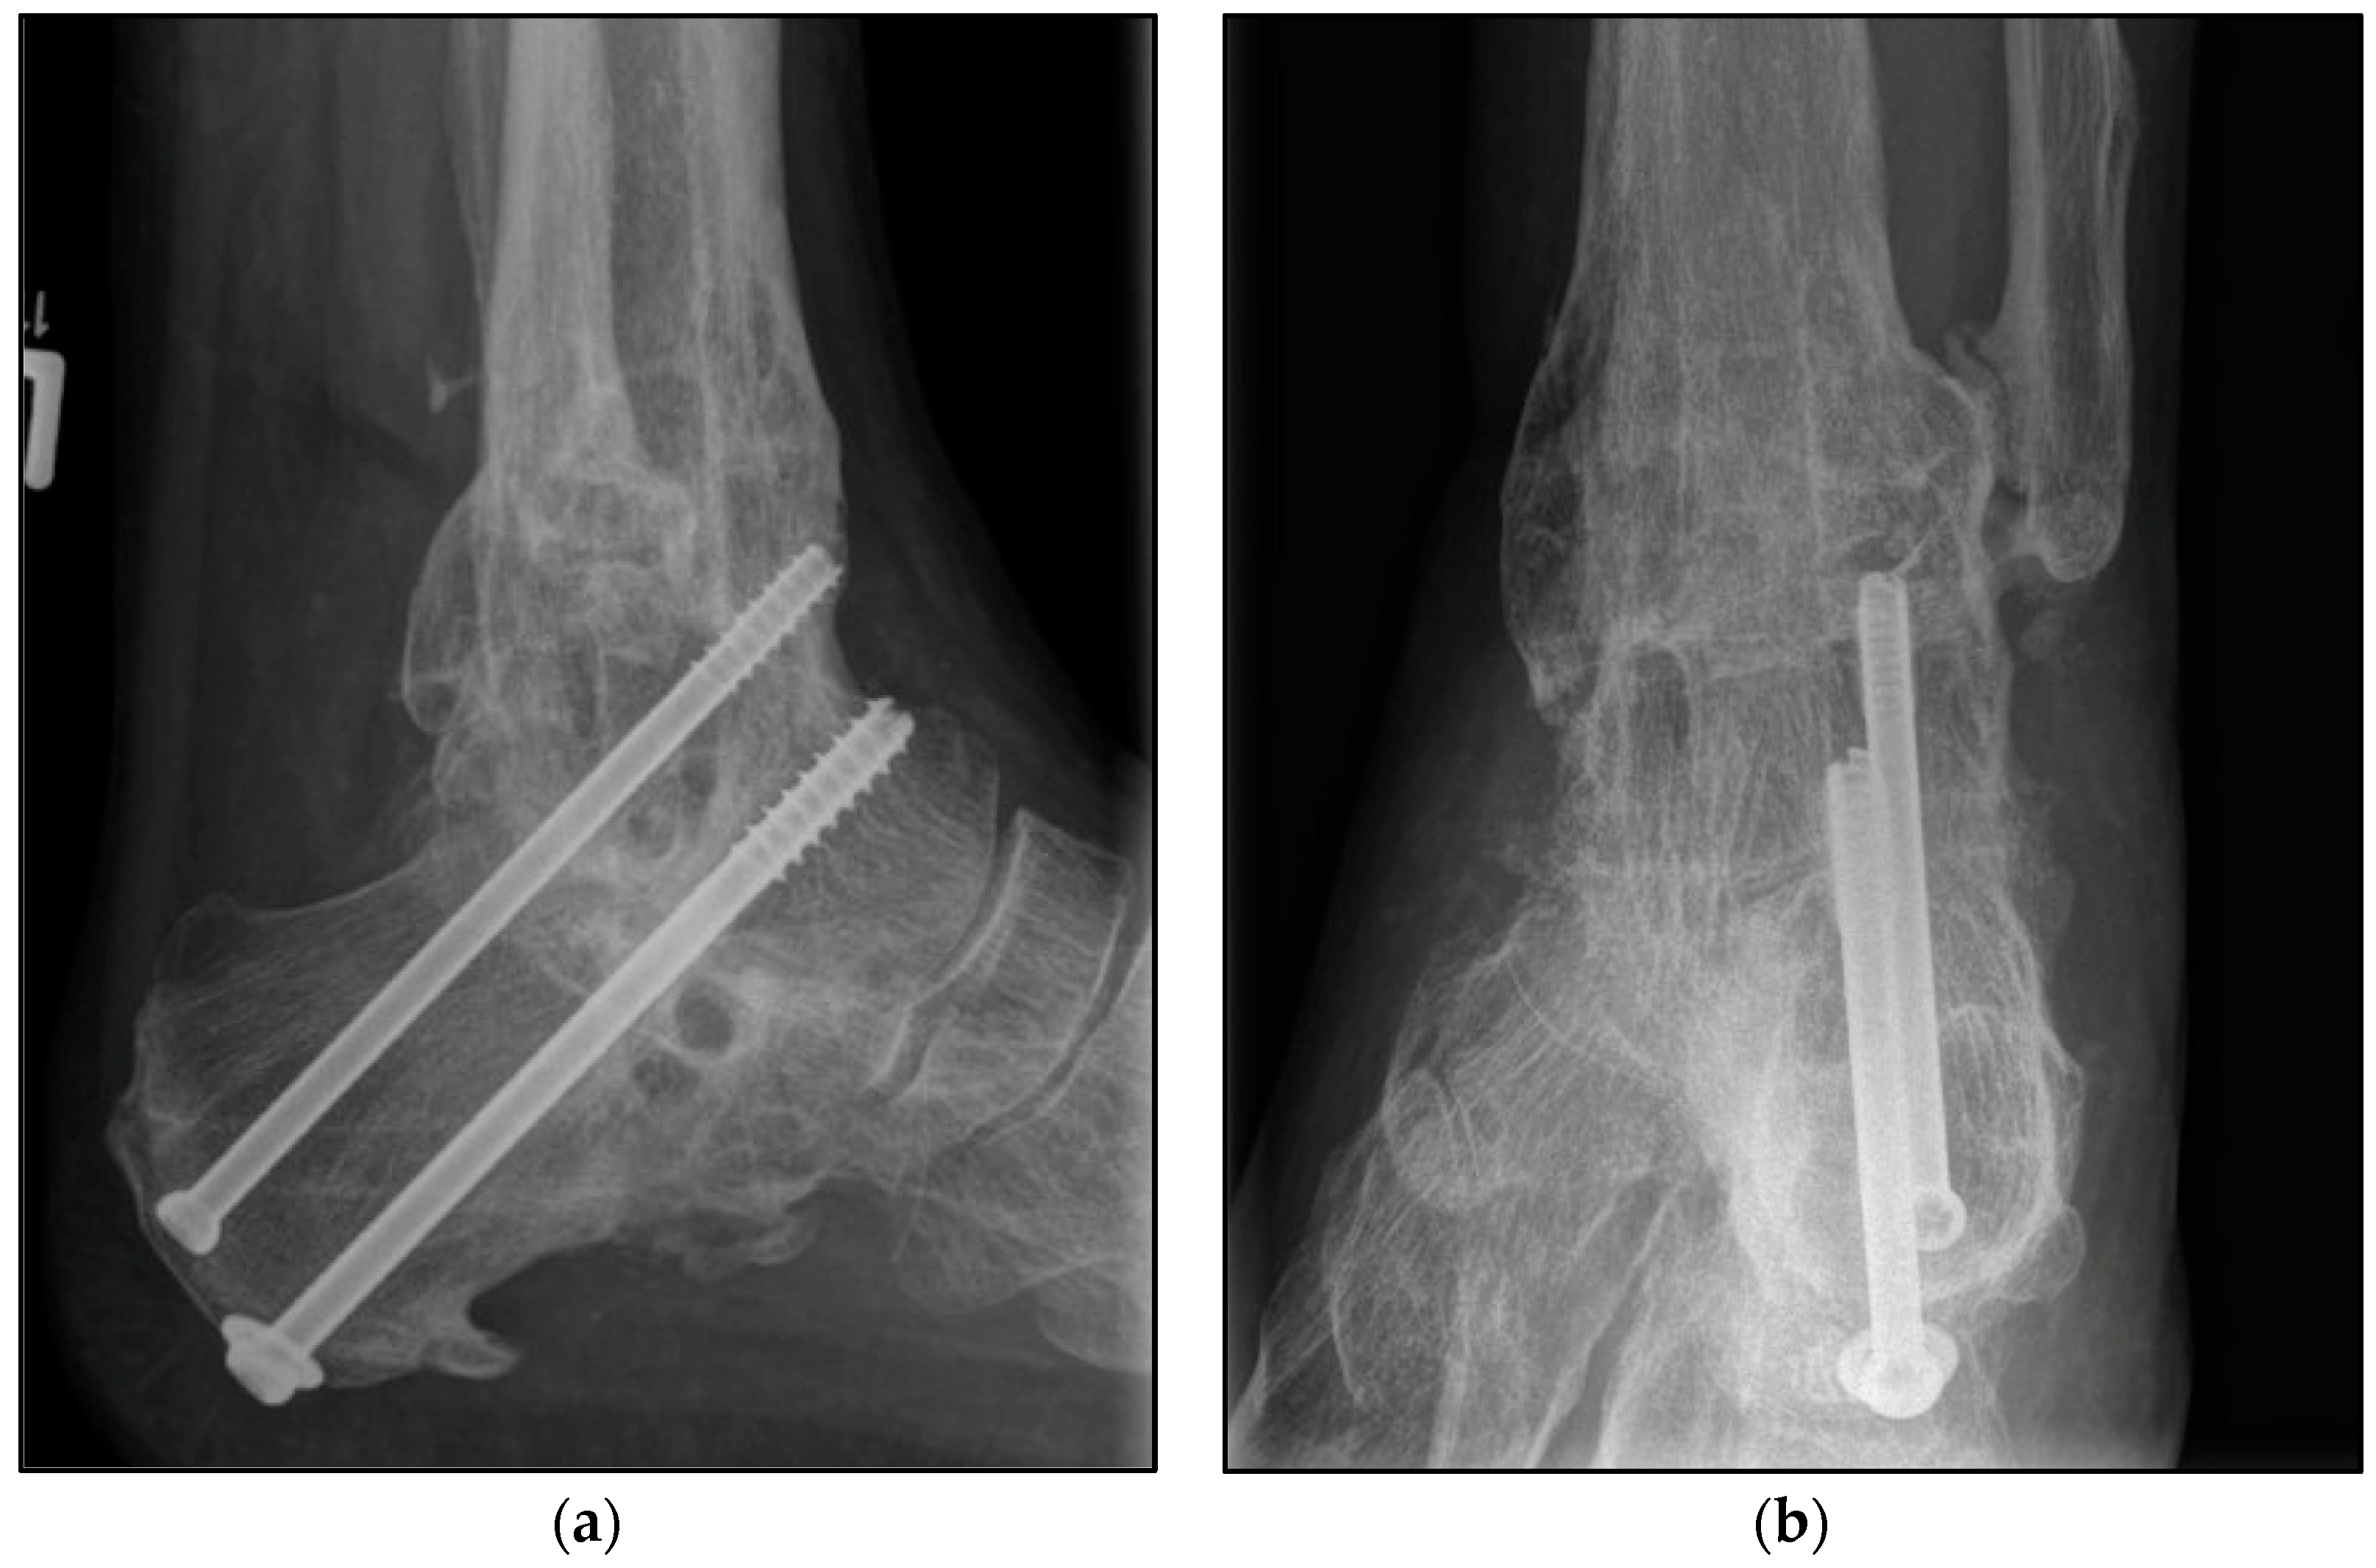

Figure 4.

Postoperative radiographic findings of end-stage posttraumatic arthritis of the left ankle with septic history of a 82-year-old male treated with a tibiotalocalcaneal arthrodesis T2™ Ankle Arthrodesis Nail, 200 × 10 mm. (a,b) Anteroposterior and lateral view; view, 5 years post operation.